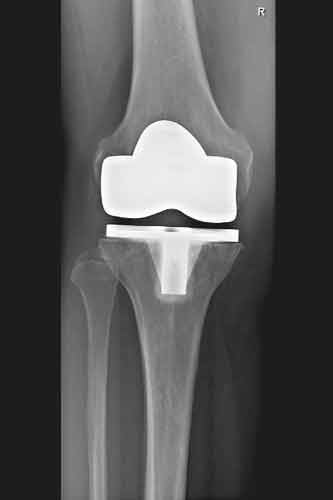

Eine Knieprothese, Knieendoprothese oder Kniegelenksprothese ist eine implantierte Prothese (Endoprothese), die das Kniegelenk ganz oder teilweise ersetzt.

Nachher

Knieröntgen ap

Z.n. Knietotalendoprothese

Knieröntgen seitlich